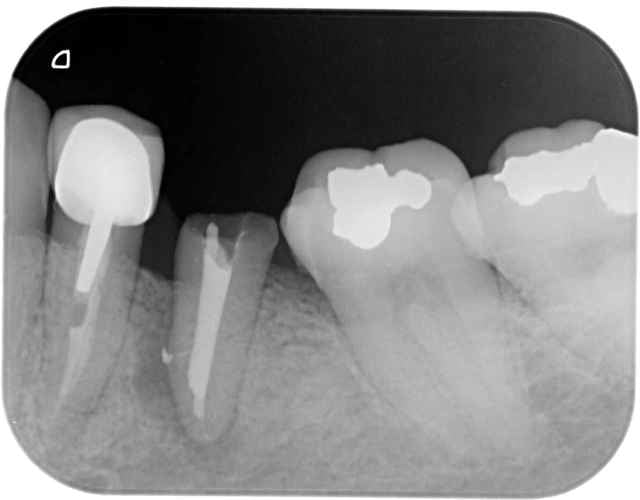

Plus sérieusement sur le premier cas le foret en place est le terminal de 12x3,5, je le trouve pas si mal l'axe 3d, mais j'ai un peu forcé sur le biomat

pour l'autre cas, je suis aussi dans l'axe,j'avais décalé le deuxieme forage en palatin pour faire une expansion

vesti, puis j'ai choisi la facilité

pxav c'est pour toi , tu te souviens

50 minutes, 3implants et 3 hemos

En 33 c'est un bouchon, j'ai tapé la corticale interne et l'artériole en meme temps et l'ai pas réussi à la traversée(l'artériole)

çà c'est un vrai probleme de 3D , vous m'avez porté la poisse

Suis moins patient que pxav, c'est un 8x3,7 je pense que çà va aller qd meme